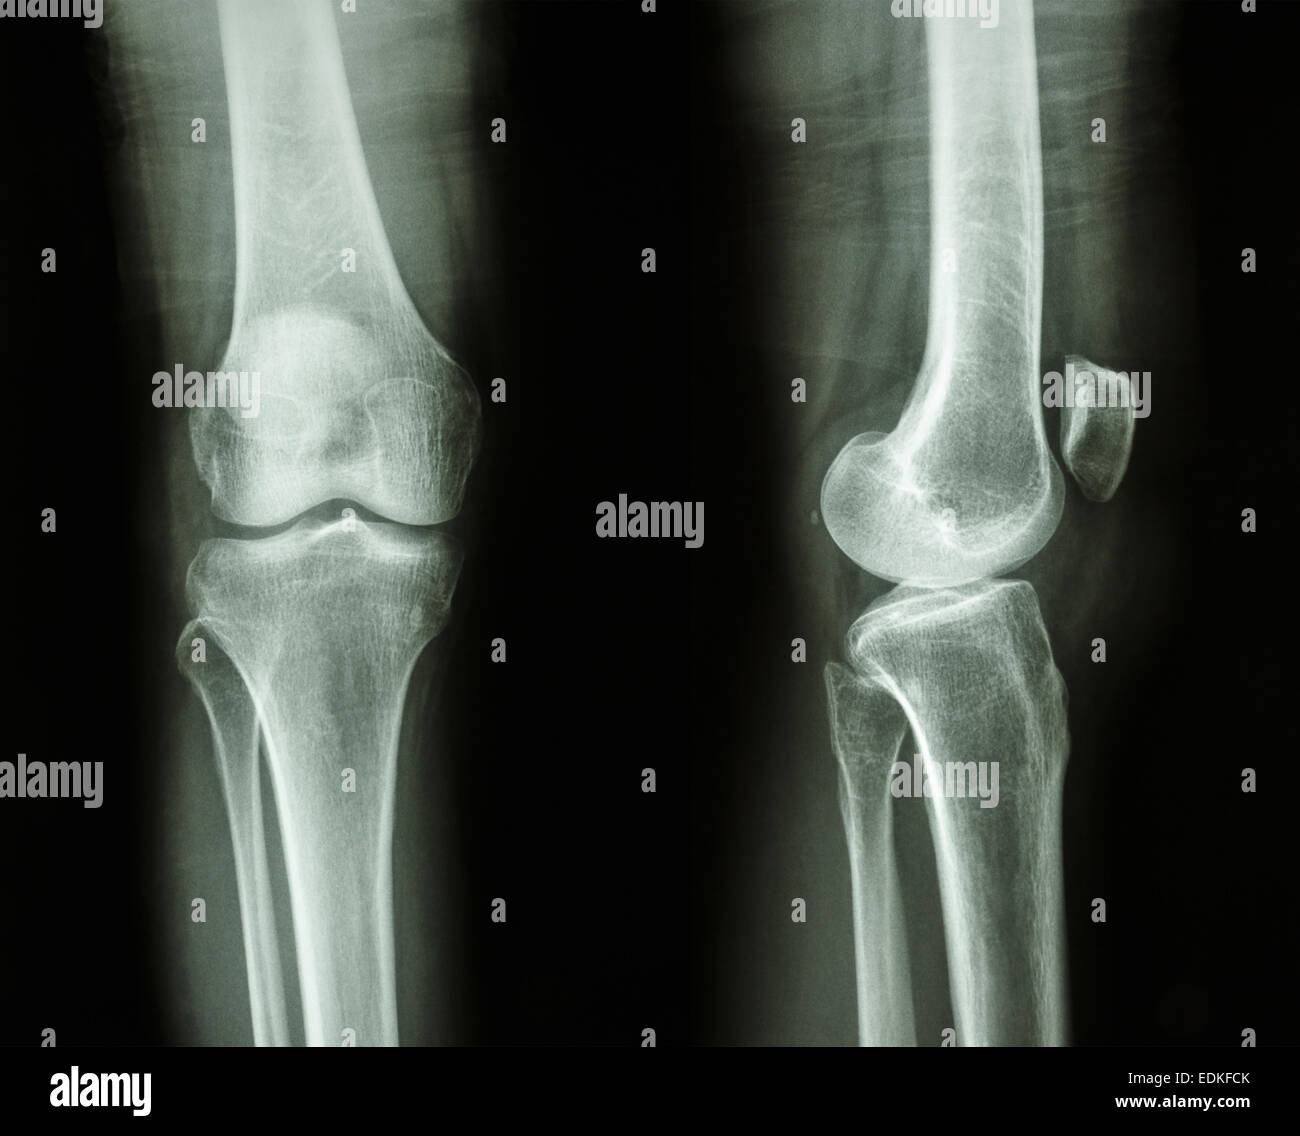

Film x-ray/AP du genou : show latérale du genou humain normal Banque D'Imageshttps://www.alamyimages.fr/image-license-details/?v=1https://www.alamyimages.fr/photo-image-film-x-ray-ap-du-genou-show-laterale-du-genou-humain-normal-77261203.html

Film x-ray/AP du genou : show latérale du genou humain normal Banque D'Imageshttps://www.alamyimages.fr/image-license-details/?v=1https://www.alamyimages.fr/photo-image-film-x-ray-ap-du-genou-show-laterale-du-genou-humain-normal-77261203.htmlRFEDKFCK–Film x-ray/AP du genou : show latérale du genou humain normal

Genou normal ( image de gauche ) et de l'arthrose du genou ( image de droite ) ( vue latérale ) Banque D'Imageshttps://www.alamyimages.fr/image-license-details/?v=1https://www.alamyimages.fr/photo-image-genou-normal-image-de-gauche-et-de-l-arthrose-du-genou-image-de-droite-vue-laterale-105598446.html

Genou normal ( image de gauche ) et de l'arthrose du genou ( image de droite ) ( vue latérale ) Banque D'Imageshttps://www.alamyimages.fr/image-license-details/?v=1https://www.alamyimages.fr/photo-image-genou-normal-image-de-gauche-et-de-l-arthrose-du-genou-image-de-droite-vue-laterale-105598446.htmlRFG3PBW2–Genou normal ( image de gauche ) et de l'arthrose du genou ( image de droite ) ( vue latérale )

Genou normal ( image de gauche ) et de l'arthrose du genou ( image de droite ) ( vue latérale ) Banque D'Imageshttps://www.alamyimages.fr/image-license-details/?v=1https://www.alamyimages.fr/photo-image-genou-normal-image-de-gauche-et-de-l-arthrose-du-genou-image-de-droite-vue-laterale-105598533.html

Genou normal ( image de gauche ) et de l'arthrose du genou ( image de droite ) ( vue latérale ) Banque D'Imageshttps://www.alamyimages.fr/image-license-details/?v=1https://www.alamyimages.fr/photo-image-genou-normal-image-de-gauche-et-de-l-arthrose-du-genou-image-de-droite-vue-laterale-105598533.htmlRFG3PC05–Genou normal ( image de gauche ) et de l'arthrose du genou ( image de droite ) ( vue latérale )

Genou normal ( image de gauche ) et de l'arthrose du genou ( image de droite ) ( vue latérale ) Banque D'Imageshttps://www.alamyimages.fr/image-license-details/?v=1https://www.alamyimages.fr/photo-image-genou-normal-image-de-gauche-et-de-l-arthrose-du-genou-image-de-droite-vue-laterale-105598514.html

Genou normal ( image de gauche ) et de l'arthrose du genou ( image de droite ) ( vue latérale ) Banque D'Imageshttps://www.alamyimages.fr/image-license-details/?v=1https://www.alamyimages.fr/photo-image-genou-normal-image-de-gauche-et-de-l-arthrose-du-genou-image-de-droite-vue-laterale-105598514.htmlRFG3PBYE–Genou normal ( image de gauche ) et de l'arthrose du genou ( image de droite ) ( vue latérale )

Genou normal ( image de gauche ) et de l'arthrose du genou ( image de droite ) ( vue latérale ) Banque D'Imageshttps://www.alamyimages.fr/image-license-details/?v=1https://www.alamyimages.fr/photo-image-genou-normal-image-de-gauche-et-de-l-arthrose-du-genou-image-de-droite-vue-laterale-105598509.html

Genou normal ( image de gauche ) et de l'arthrose du genou ( image de droite ) ( vue latérale ) Banque D'Imageshttps://www.alamyimages.fr/image-license-details/?v=1https://www.alamyimages.fr/photo-image-genou-normal-image-de-gauche-et-de-l-arthrose-du-genou-image-de-droite-vue-laterale-105598509.htmlRFG3PBY9–Genou normal ( image de gauche ) et de l'arthrose du genou ( image de droite ) ( vue latérale )